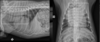

What is shown in these images?

A

(sub)aortic stenosis

-left heart enlargement

-elongation of cardiac silhouette

-increased prominence of aortic arch